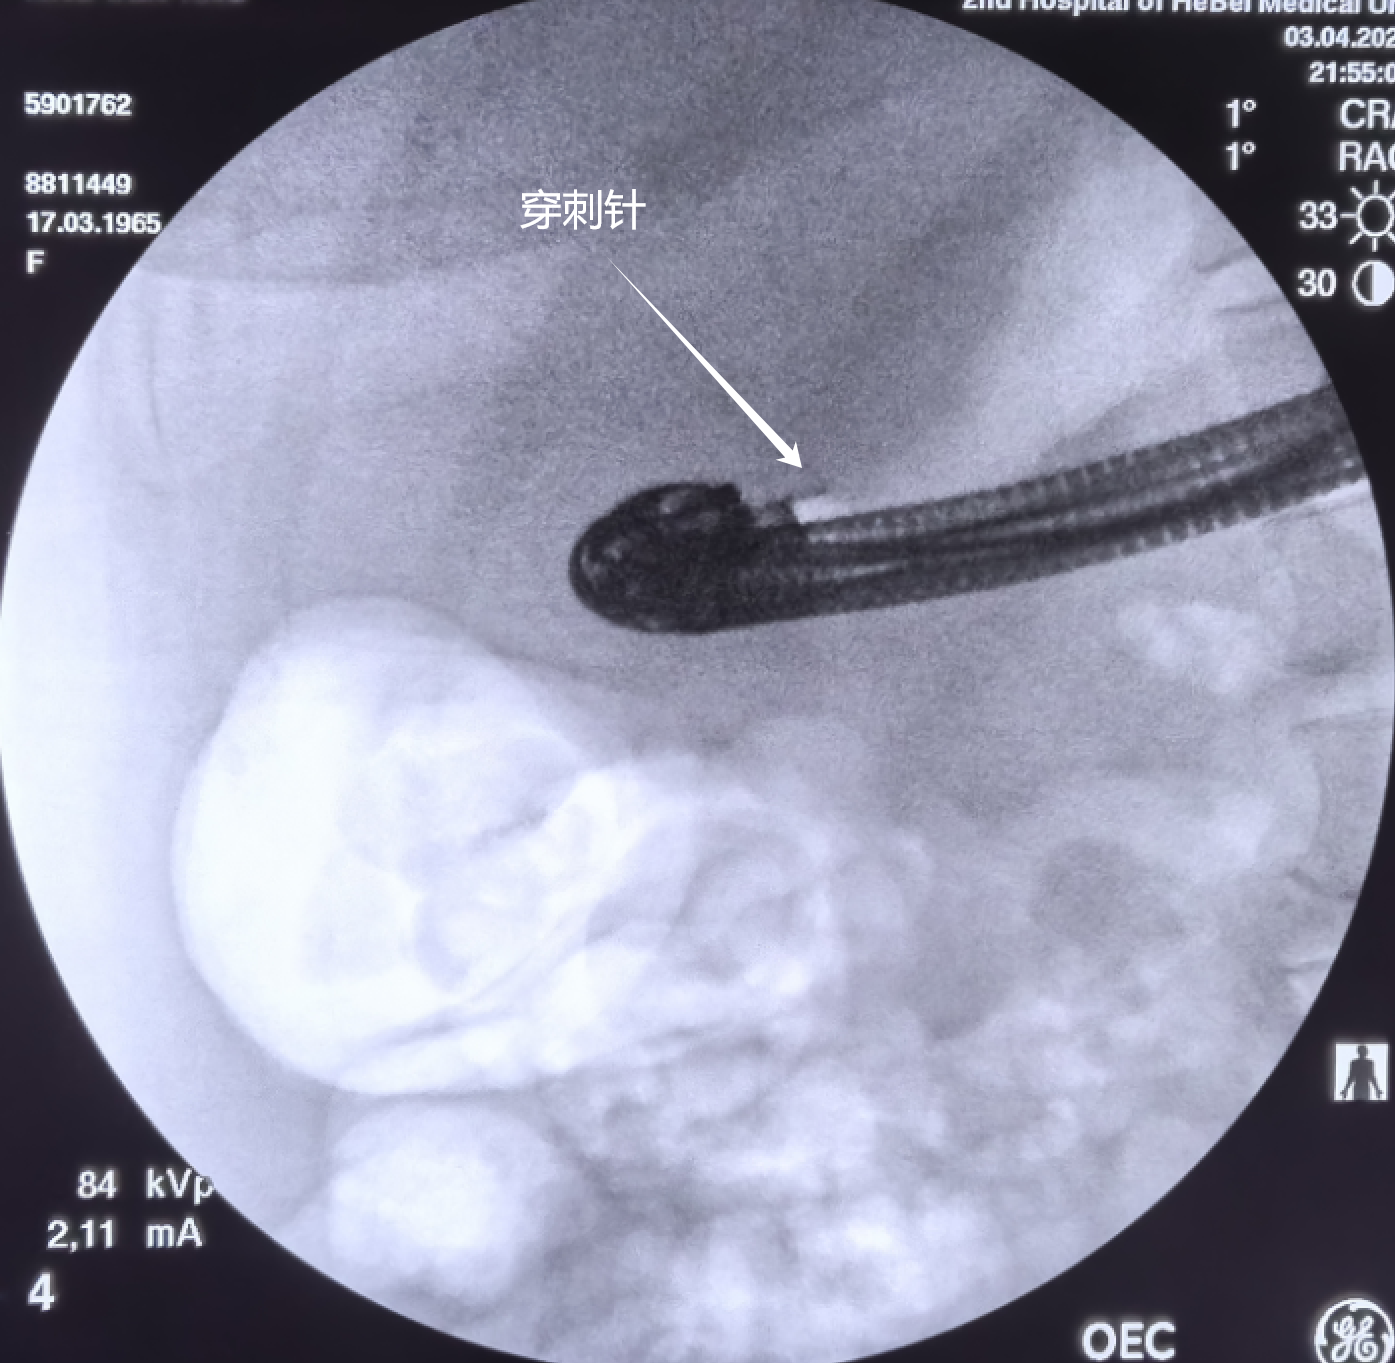

囊肿切开刀切开后,置入双导丝

可是扩张的时候需要注意了,内镜下扩张水囊在胃腔不长

所以现在只扩开了胃壁

调整水囊进入囊肿,再次扩张

如果囊肿壁没有扩张开,后续的支架等有可能由于前面的猪尾支架弯曲使导丝脱出然后支架放进网膜囊了